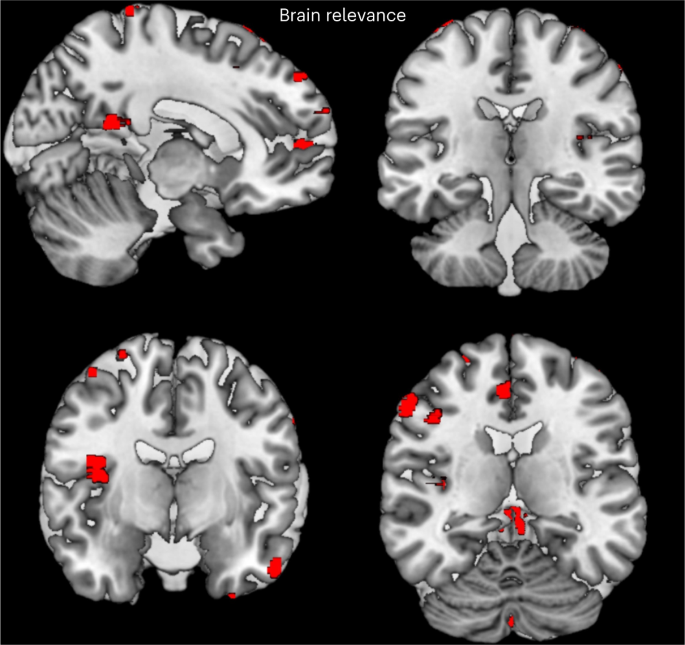

Implementation of the layer-wise relevance propagation (LRP) algorithm for multilayer neural networks, as described in Bach et al.38, showed that voxels with the highest contribution to the difference between patients and HC participants (that is, those with the highest relevance for the classification decision) were located in the cerebellum, anterior and posterior midline areas, frontotemporal areas and right insula (Fig. 1 and Supplementary Tables 5 and 6). In addition, we investigated cortical biomarkers for the general psychopathology in gray matter (GM), WM and CSF. The regions of interest were extracted using the AAL-VOIs atlas (https://doi.org/10.1006/nimg.2001.0978). We used the Johns Hopkins University (JHU) WM tractography atlas39 to identify the WM tractography identified by the LRP.

The relevance of the voxels calculated from the LRP are overlaid and rendered in a GM template using the MRIcron toolbox.

The final images were visualized using the MRIcron toolbox (MRIcron; v1.020190902 for Windows). Visualizations of the classification results on the holdout dataset are presented in Fig. 1. The regions of interest were extracted using the AAL-VOIs atlas (AAL-VOIs). GM, WM and CSF were investigated for cortical biomarkers in psychosis. We used the JHU WM tractography atlas39 to identify the WM tractography identified by the LRP algorithm.